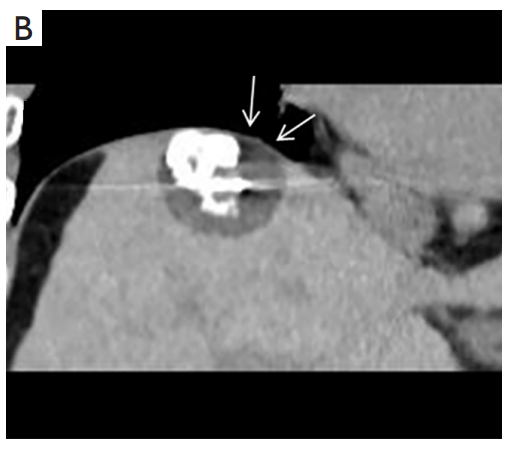

背景:肝癌是中國最常見(jiàn)的惡性腫瘤之一,發(fā)病率和死亡率都很高。雖然手術(shù)切除是最好的治療方法,但大多數患者處于晚期或直到住院才有手術(shù)指征。對于單個(gè)腫瘤直徑小于5厘米的患者,微創(chuàng )治療與手術(shù)切除效果相當;多個(gè)病灶小于3個(gè),單個(gè)病灶最大直徑小于3cm;不侵犯血管、膽管、鄰近器官和遠處轉移。雖然一些傳統消融技術(shù)方式可以使部分患者受益,但不適用于特殊部位肝癌(定義為毗鄰大血管、肝外臟器和重要結構的腫瘤)的治療。冷凍消融作為一種相對較新的治療方式,具有明顯的冰球效果、療效好、激活抗腫瘤免疫、并發(fā)癥發(fā)生率低等優(yōu)點(diǎn),尤其適用于特殊部位肝癌患者的治療。我們的研究目的是探討CA治療特殊部位肝癌的安全性、可行性和有效性。

① 在我們的研究中,技術(shù)成功率為100%。動(dòng)態(tài)增強MR檢查隨訪(fǎng)1個(gè)月,66例患者首次技術(shù)有效率為65例(98.5%),MR影像學(xué)未發(fā)現外周臟器損傷。中位隨訪(fǎng)時(shí)間14個(gè)月(范圍2-28個(gè)月)。高危部位肝癌局部腫瘤進(jìn)展率曲線(xiàn):6、9、15和24個(gè)月的累積局部腫瘤進(jìn)展率分別為10.2%、16.5%、20.9%和30.5%。